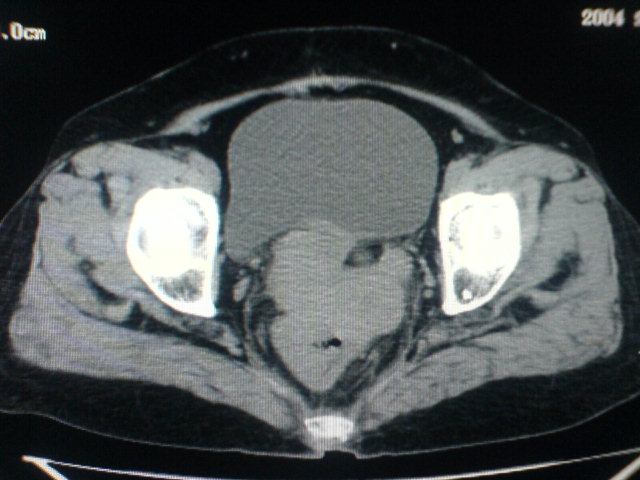

患者为老年女性,肿块最大层面不是位于宫颈,但宫颈偏后方有一囊状低密度影,肿块主要位于乙状结肠及直肠,所以考虑乙状结肠及直肠癌浸犯宫颈可能性大。

患者女性60岁 病史不详

宫颈癌侵犯直肠可能

考虑子宫内膜癌浸犯直肠。

考虑直肠癌侵及宫颈可能;建议增强扫描。

支持考虑宫颈癌上下前后通吃

考虑:直肠及乙状结肠癌侵及宫颈,囊性转移(假性粘液瘤)

支持宫颈癌侵犯直肠。

考虑直肠及乙状结肠癌侵犯邻近结构。